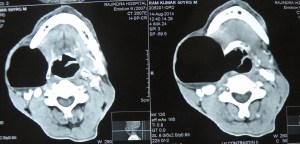

Repaired a large laryngocele for the first time in life!. Had never seen it actually before this one. An old man ( a chronic smoker) had been having a large swelling on the right side of the neck for a long time, and now had been experiencing some pain and hoarseness of voice. ENT examination revealed an internal component of the laryngocele too which had displaced the larynx to the left.